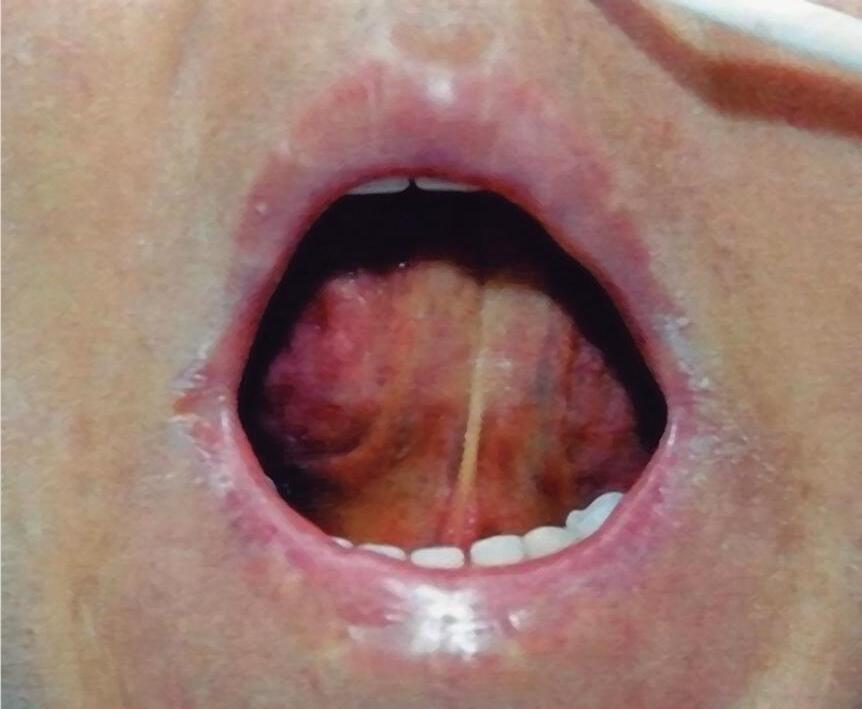

Fig. 2-31. Visão endoscópica de úlcera péptica gástrica (a,b); duodenal (c,d) com sangramento e substrato anatomopatológico do estômago com sangue e úlcera péptica (e,f). (Fonte: Arquivo do Departamento de Cirurgia-FCM/ unicamp.)